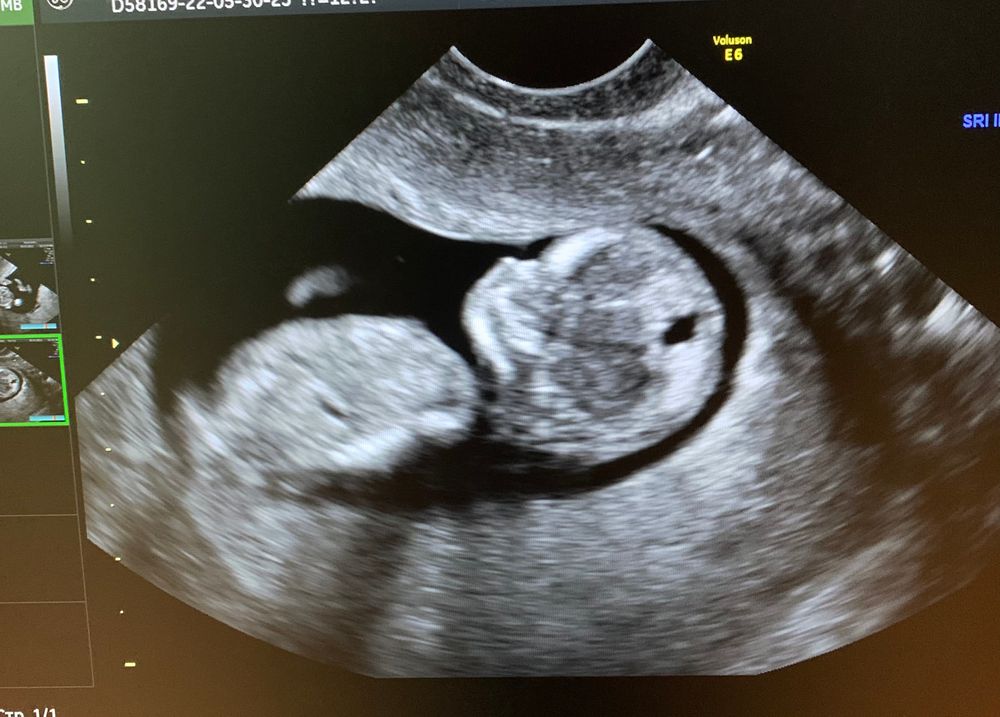

Вот и прошли мы 1-ый скрининг, может будут у кого ни будь предположения кого же мы все таки ждём?😉по УЗИ срок почему то меньше на 5 дней, а так сказали что все хорошо

Если это не бедренная кость (нога), то обычно так у мальчика. Но в данном случае, если присмотреться, то ясно, что это всё-таки кость бедра.

Не понятно это кость или бугорок , если бугорок, то мальчик 👶🏻 а так по профилю на девочку похоже)